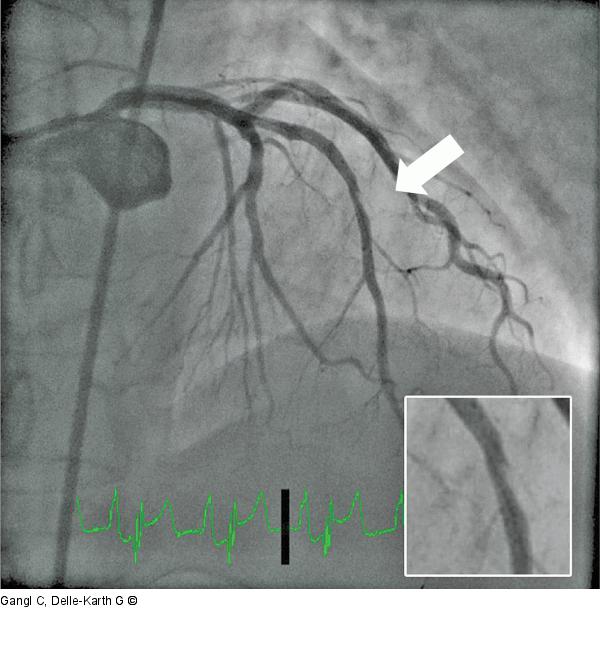

Abbildung 3: ABSORB Angiographisch zeigt sich eine Stufenbildung im Bereich des distalen ABSORB. |

Angiographisch zeigt sich eine Stufenbildung im Bereich des distalen ABSORB. |